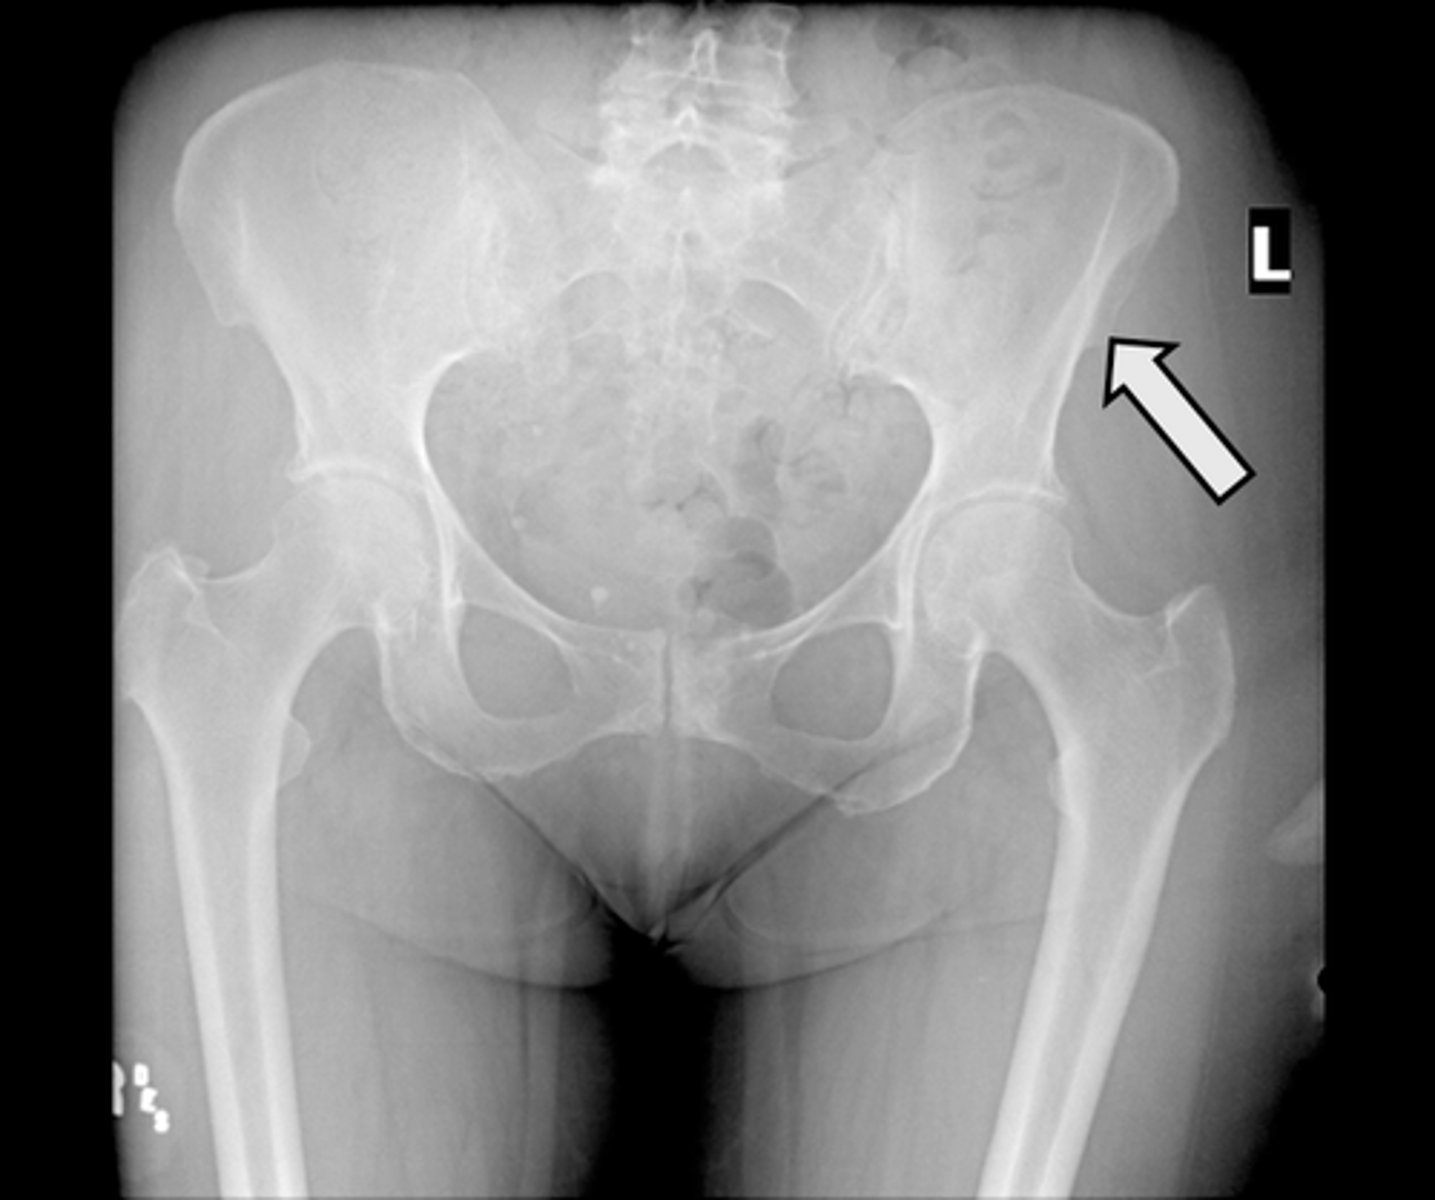

AP pelvis

What is the image?